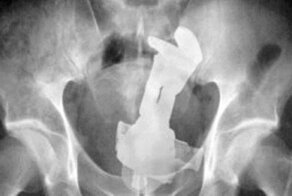

- Самые странные предметы, извлеченные врачами из пациентов